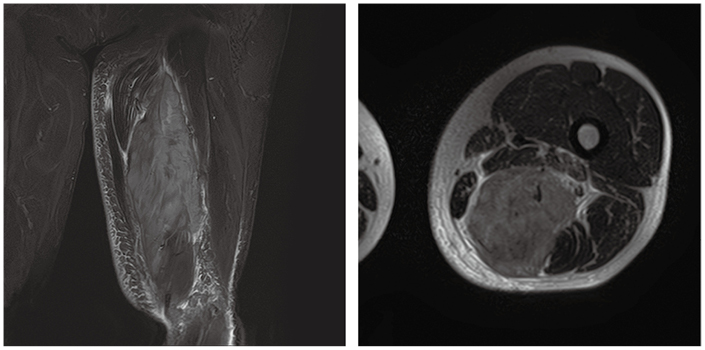

症例2

症例2の患者情報

30歳代,男性。

約3カ月前から明らかな誘因なく右大腿後面の痛みが出現。その後の経過観察で同部に腫瘤を認めたため,MRI検査を施行した。